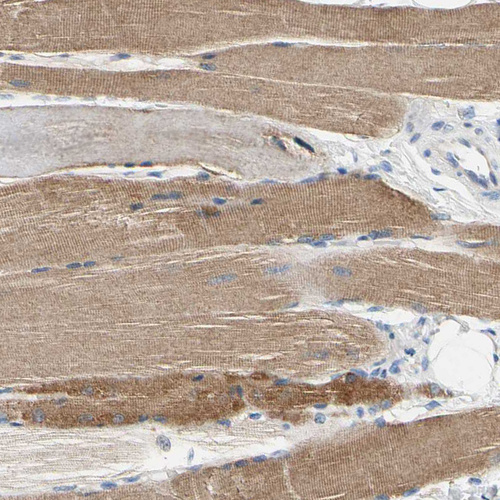

Immunohistochemical staining of human skeletal muscle shows moderate cytoplasmic positivity in myocytes.